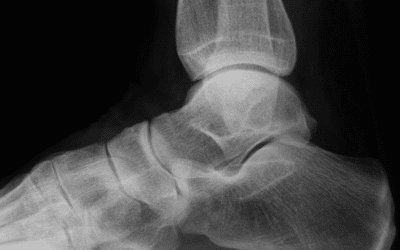

Hielspoor

Hielspoor behandelen Een Fasciitis plantaris of hielspoor is een haakvormige verkalking van de peesplaat aan het hielbeen, die erg vervelend kan zijn maar goed te behandelen is. Deze verkalking ontstaat door overmatige rek op de peesplaat en is vooral voelbaar bij...